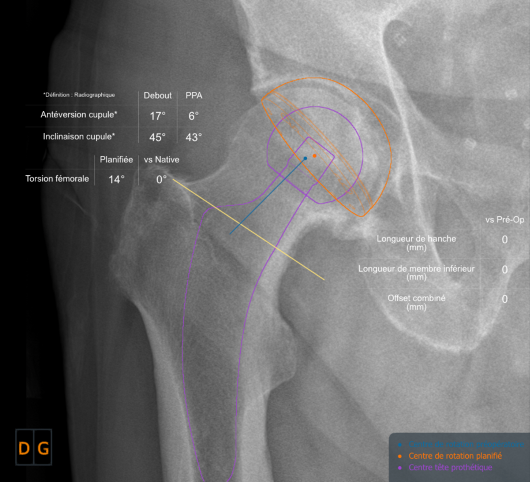

Planning - The intervention begins before the incision, with the preparation. As Franklin said “If you fail to plan, you are planning to fail”. Pre-operative planning is an integral part of the success of the operation, in that it involves assessing the native hip parameters (which should be restored) and anticipating any peri-operative difficulties. This planning means that the precise size of the final stem can be determined, ensuring optimal intramedullary filling, and the correct height of the femoral neck cut can be identified. Under-sizing risks secondary subsidence, especially in somewhat valgus tilted femurs . Stem positioning must follow the calcar rather than the diaphyseal axis, which will enable the femoral offset to be restored. Restoring an optimal overall offset also depends on the depth to which the socket is burred, as this may sometimes need to be compensated for on the femoral side. Finally, it is important to take femoral torsion into account. All this points to the value of 3-dimensional planning systems that take these parameters into account (EOS or CT scan), and are more complete than the conventional practice of sketching on AP radiographs.